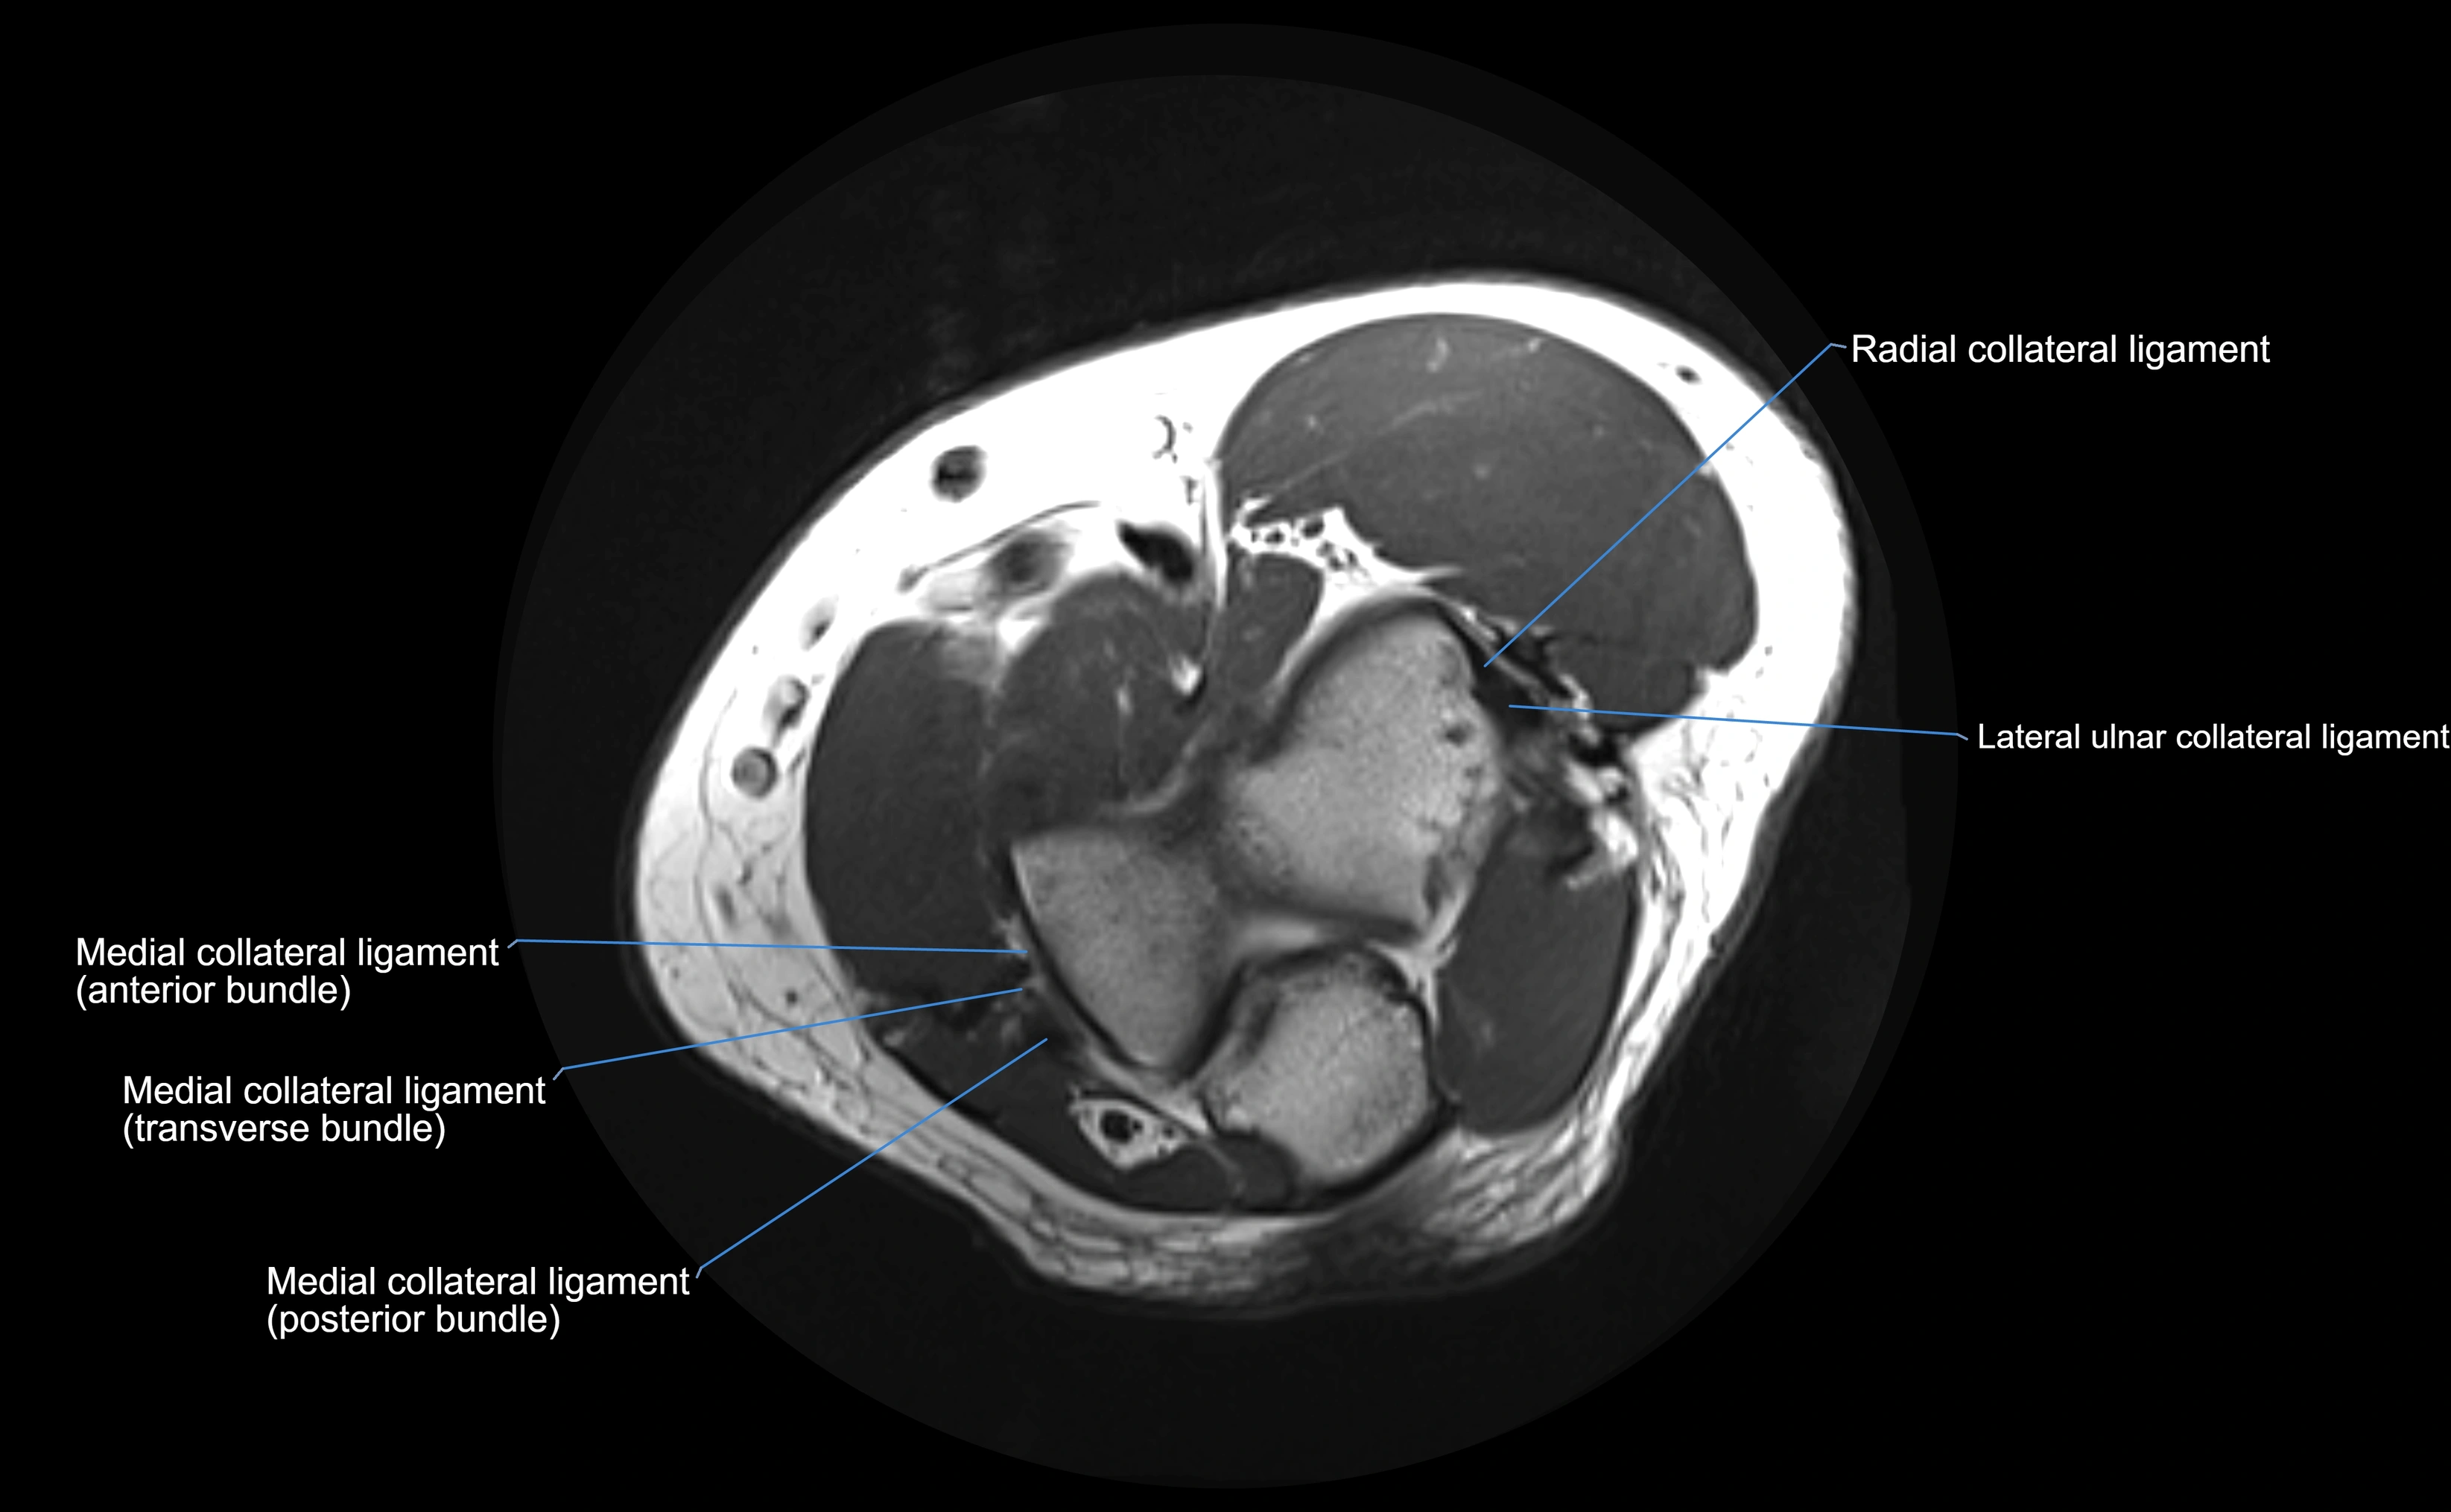

MRI Appearance

T1-weighted images:

• Ligament: low signal intensity (dark), appearing as a continuous band around the radial head.

• Adjacent fat and marrow: bright, creating contrast with the ligament.

• Thickening or disruption indicates injury or fibrosis.

• Joint capsule and synovium seen as thin low-signal lines contiguous with ligament margins.

T2-weighted images:

• Ligament: low signal (dark) with clear delineation from joint fluid.

• Fluid or edema: bright hyperintense, separating or surrounding the ligament in partial tears.

• Complete tear: discontinuity or non-visualization of ligament fibers, often with joint effusion.

STIR:

• Normal ligament: dark band encircling radial head.

• Pathology: bright hyperintense periligamentous signal suggesting edema, sprain, or partial tear.

Proton Density Fat-Saturated (PD FS):

• Normal: dark, well-defined band outlining the radial head.

• Partial tear: irregular or bright hyperintense signal within or adjacent to ligament fibers.

• Joint effusion and reactive synovitis appear bright and are well visualized.

MRI Arthrogram Appearance

• Contrast outlines the proximal radioulnar joint and radial head recess.

• Normal ligament appears as a dark ring surrounding the radial head, containing the injected contrast within the joint cavity.

• Partial tear: contrast extends along the ligament or beneath its fibers.

• Complete tear or subluxation: contrast extravasates around the radial head or ulna, indicating discontinuity.

• Detects capsular defects, instability, or synovial invagination with high sensitivity.